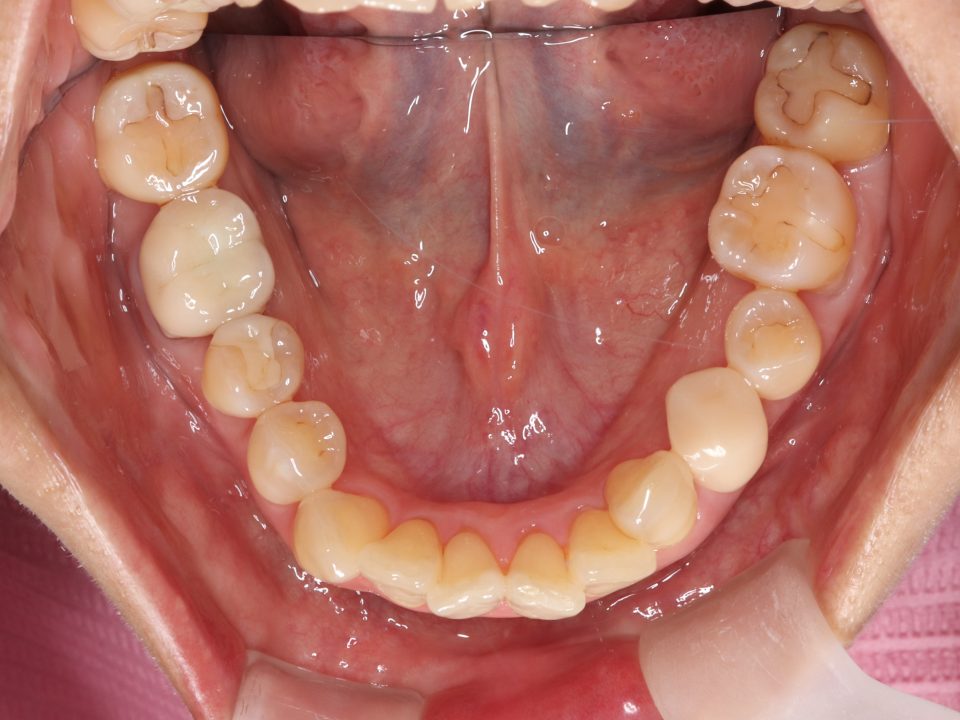

矯正治療前

マウスピース型の矯正治療装置を使用し、歯のやすり掛け(IPR)を行いました。

現在はマウスピース型のリテーナーでで後戻りの防止をして定期的にチェックをしています。